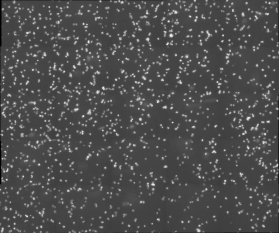

北京眼科研究所致力于探索眼科疾病的发病机制和治疗方法,其中免疫学研究是其重要方向之一。在一项关于小鼠巨噬细胞的研究中,科研人员需要对细胞进行长时间的动态监测,以观察其在免疫反应中的行为变化。然而,传统的显微镜在长时间成像时往往面临成像速度慢、清晰度不足以及软件操作复杂等问题,这些问题严重限制了研究的进展。

MCS31配备了10XPH和20PH高分辨率物镜,能够提供清晰、细腻的细胞图像,满足基本的细胞成像需求。